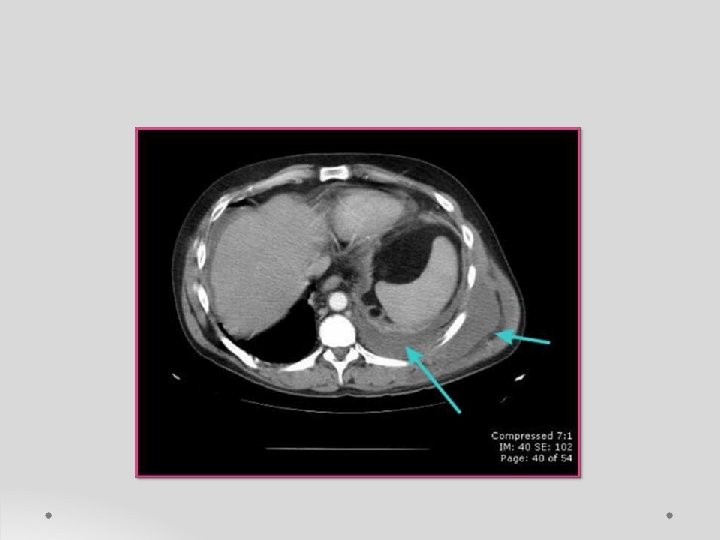

o. Sonography or CT imaging o Chest CT imaging to detect : - pleural fluid and image the airways - guide interventional procedures